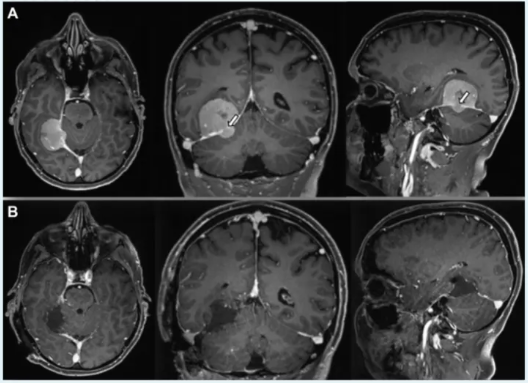

46岁男性小脑幕脑膜瘤患者

术前临床表现:长期慢性头痛,影像学检查发现小脑幕脑膜瘤沿小脑幕倾斜生长(图A),伴有少量颞下成分侵入小脑幕区域(白色箭头指示)。

术后评估结果:术后核磁共振成像(B)显示,通过极外侧幕下小脑上入路实现肿瘤全切除。